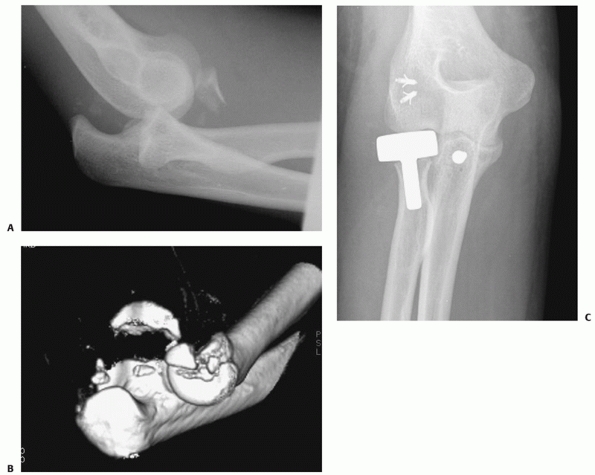

![]() |

FIGURE 32-11

Early failure and nonunion are common after open reduction an internal fixation of fractures that involve the entire radial head (Mason type 3), particularly those fractures that create more than three articular fragments. A. This displaced fracture was part of a fracture-dislocation. B. Stable internal fixation was achieved initially. C. Six months later, the plate was broken and the radial neck remained unhealed. |